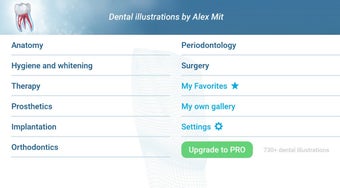

تطبيق مجاني لنظام الأندرويد، من قبل أليكس ميت.

تم إنشاء هذا التطبيق بواسطة أليكس ميت للأطباء الأسنان وطلاب طب الأسنان والمرضى. كما يمكن استخدامه أيضًا من قبل المهنيين الطبيين الآخرين.

كما يمكن نقل الموضوع المفضل لديك إلى قسم المفضلة.

يستند التطبيق على مبدأ عرض الشرائح. يحتوي كل موضوع على 3-9 صور. يمكن عرض صور أي موضوع في أي وقت.